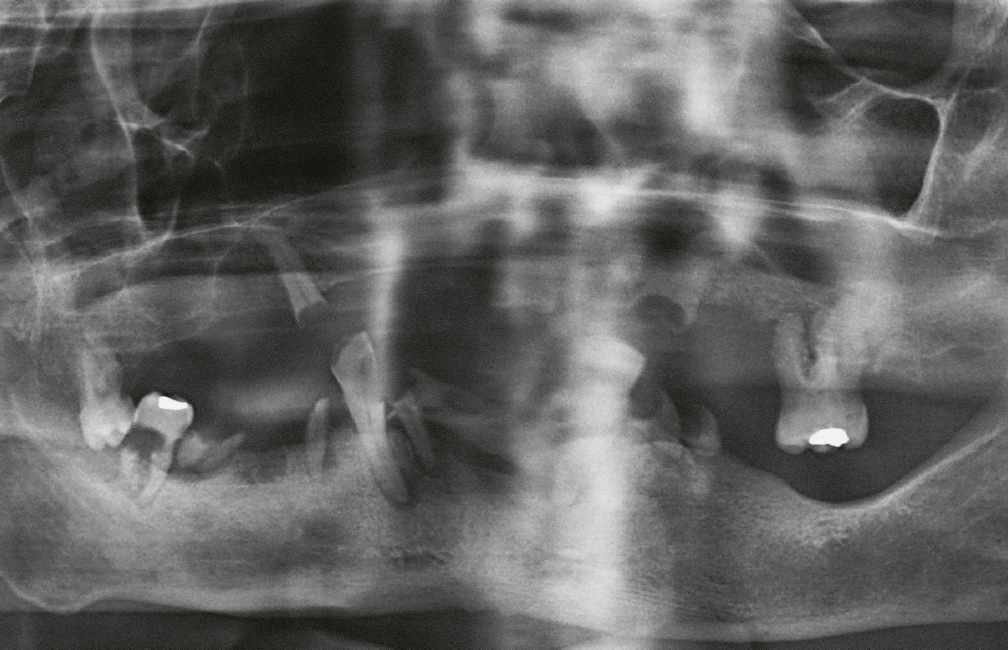

Abb. 11 Patient 4: Desolater Zahnstatus des prothetisch und konservierend nicht versorgten Patienten mit multiplen kariösen Zähnen, elongierten Zähnen, Wurzelresten, apikalen Ostitiden. Mit dem Nachweis der Bakterien aus der Streptococcus-anginosus-Gruppe und Fusobacterium nucleatum wurde der Nachweis für eine odontogene Infektion ausgehend von den desolaten, nicht erhaltungswürdigen Zähnen erbracht. Nach Stabilisierung des Patienten erfolgte eine Zahnsanierung.

Tab. 1 Patient 4: Bei der Entlastung des Hirnabszesses wurde ein Abstrich durchgeführt. Mikrobiologisch wurden in der Kultur zahlreiche Bakterien aus der Streptococcus-anginosus-Gruppe (grampositive Aerobier) und Fusobacterium nucleatum (gramnegative Anaerobier) nachgewiesen. Im Antibiogramm zeigten sich die Bakterien aus der Streptococcus-anginosus-Gruppe sensibel gegenüber Penicillin, Ceftriaxon und Clindamycin. Auch Fusobacterium nucleatum zeigte sich sensibel gegen die getesteten Antibiotika.

Streptococcus-anginosus-GruppeSensibilitätFusobacterium nucleatumSensibilitätPenicillinsensibelPenicillinsensibelCeftriaxonsensibelAmoxicillin/SulbactamsensibelClindamycinsensibelPiperacillin/Tazobactamsensibel––Imipenemsensibel––MetronidazolsensibelZu den am häufigsten nachgewiesenen aeroben Bakterien odontogener Infektionen gehören die Viridans-Streptokokken und Staphylococcus aureus, aber auch Neisseria spp., Klebsiella spp., Enterococcus faecalis, Capnocytophaga gingivalis, Aggregatibacter actinomycetemcomitans, Eikenella corrodens und Lactobacillus spp.3,21–23. Bei den anaeroben Bakterien dominieren Peptostreptococcus und Prevotella spp. neben Porphyromonas spp.; Bacteroides und Fusobacterium spp. können neben Veillonella und Eubacterium spp. sowie Campylobacter spp. ebenfalls nachgewiesen werden3,4,19. Auch Hefepilze konnten in odontogenen Infektionen nachgewiesen werden, wobei keine Resistenzdaten zu den nachgewiesenen Hefepilzen vorliegen und die pathophysiologische Rolle unklar ist4,9,24.